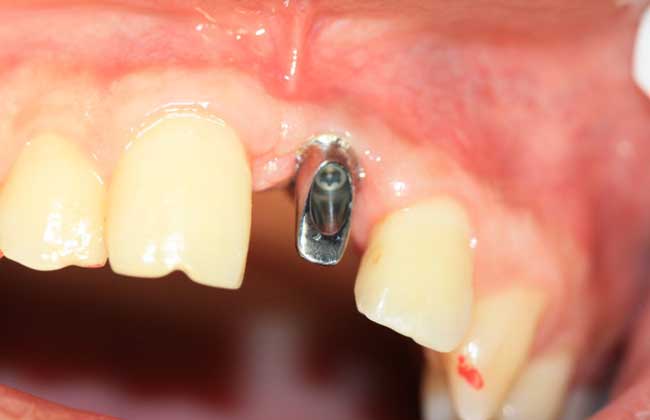

1、导致感染:种植牙包括下部的支持种植体和上部的牙修复体两部分,其危害多因手术区或手术器械污染及其它并发症诱发感染。

2、牙龈增生:种植牙由于基台穿龈过少或基台与桥架连接不良造成局部卫生状况差,长期的慢性炎性刺激可致牙龈增生。

3、固位性好:种植牙齿不使用传统镶牙的卡环或牙套,人工牙与牙槽骨紧密结合,像真牙一样扎根在口腔里,具有很强的固位力与稳定性。